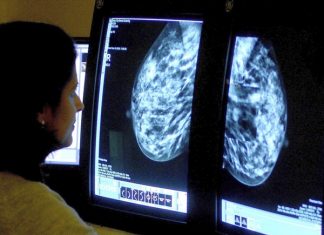

Less Fat, More Fruit May Cut Risk of Dying of Breast...

For the first time, a large experiment suggests that trimming dietary fat and eating more fruits and vegetables may lower a woman's risk of...